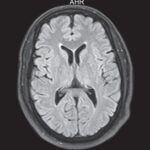

En esta investigación que se viene señalando, se puede mencionar el caso de un joven de 16 años, con alteración aguda del estado mental por inhalación de vapor de heroína. Se le efectuó una RM que evidenció hiperintensidades en T2 de la sustancia blanca simétrica difusa infratentorial y supratentorial. El diagnóstico clínico en este caso fue rabdomiólisis, que afecta predominantemente la musculatura posterior del cuello(21) (ver Imágenes 11 y 12).

Otro caso que merece ser comentado es el de un adolescente de 15 años que presentó encefalopatía y signos extrapiramidales por ingestión de metadona. La RM evidenció focos de infartos agudos en el caudado y putamen, así como infartos corticales de la línea divisoria de aguas parietales(21) (ver Imagen 13).